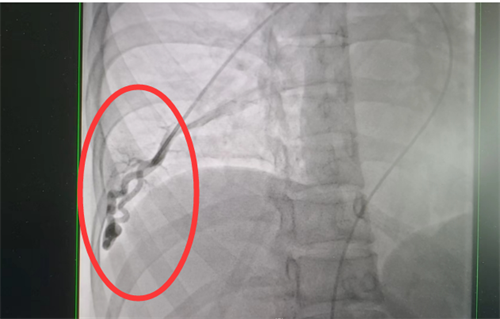

目前治疗肺动静脉瘘的方法有两种—介入手术及外科切除,可根据患者具体情况选择合适干预方式。通过积极处理,梁瑶脑梗症状得到控制,随后转入立博体育

外周血管介入科进行介入手术治疗。此类手术难度大,风险高,经科室团队仔细讨论,定下最佳方案,为患者顺利实施了肺动静脉瘘封堵术,手术全程4小时,术后平稳回到病房。术后复查肺动静脉瘘已消失不见,经过后续的对症治疗和护理,梁瑶恢复良好,于5月上旬出院。

术前肺动静脉瘘造影